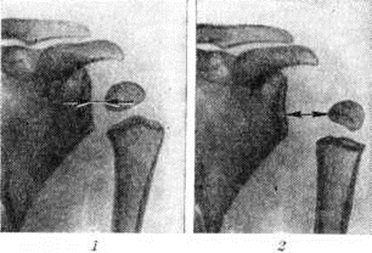

Рентгенологическое исследование позволяет установить отклонения в состоянии костей плечевого сустава в начальных фазах заболевания и проследить за дальнейшими их изменениями. Уже в первые месяцы жизни до появления ядер окостенения головки плечевой кости рентгенологически у ребёнка можно обнаружить симптом разболтанности плечевого сустава, основным признаком которого является увеличение расстояния между краем проксимального метафиза плечевой кости и суставной впадиной лопатки, что сравнительно легко устанавливается при сопоставлении рентгенограмм (или электрорентгенограмм) больного сустава с симметричным здоровым (рисунок 1). После появления ядра окостенения головки плеча изучению и сравнению подлежит расстояние от ядра окостенения до суставной впадины.

В связи с разболтанностью сустава и поворотом руки внутрь происходит проекционное смещение ядра окостенения головки плеча (рисунок 2), которое иногда приводит к ошибочному заключению о развитии при Дюшенна – Эрба паралич эпифизеолиза. В дальнейшем отчётливо выявляется остеопороз (смотри полный свод знаний) и атрофия костей плечевого пояса, особенно головки плеча и суставного отростка лопатки. Сравнительное изучение рентгенограмм плечевых суставов ребёнка показывает, что кости больной конечности уменьшены в размерах, порозны и атрофичны.

Рис. 1.

Рентгенограммы плечевых суставов: 1 — нормальное отстояние метафиза плеча от суставной впадины лопатки; 2 — смещение плечевой кости книзу при разболтанности плечевого сустава. Стрелки — расстояние между плечевой костью и суставной впадиной лопатки.

Рис. 2.

Рентгенограммы плечевых суставов. Положение ядра окостенения эпифиза плеча: 1 — нормальное; 2 — смещение ядра окостенения при повороте конечности внутрь.